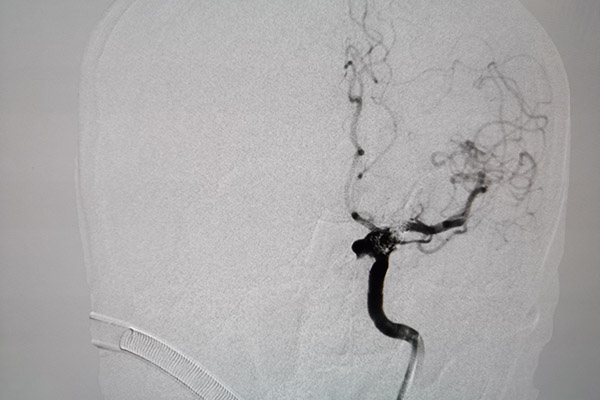

確定手術方案后,由吳剛副主任醫師主刀對患者進行血流導向裝置置入+彈簧圈栓塞術治療,經精確測量,選擇了一枚與載瘤動脈匹配良好的血流導向裝置,手術中裝置一次到位并且順利釋放。術中造影復查發現病變頸動脈內血流受血流導向裝置引導基本恢復正常流徑,整個手術過程十分順利,患者獲得了理想的血管重建。

由于該項技術操作難度系數較大,對術者的技術要求很高。所以目前市內僅有柳州市人民醫院可以開展,此次介入是我院成功使用血流導向裝置完成第五例巨大顱內動脈瘤栓塞術,體現了柳州市人民醫院神經外科在腦血管疾病的救治方面又上新水平,該項技術的開展為顱內巨大動脈瘤患者的治愈帶來了新的希望。